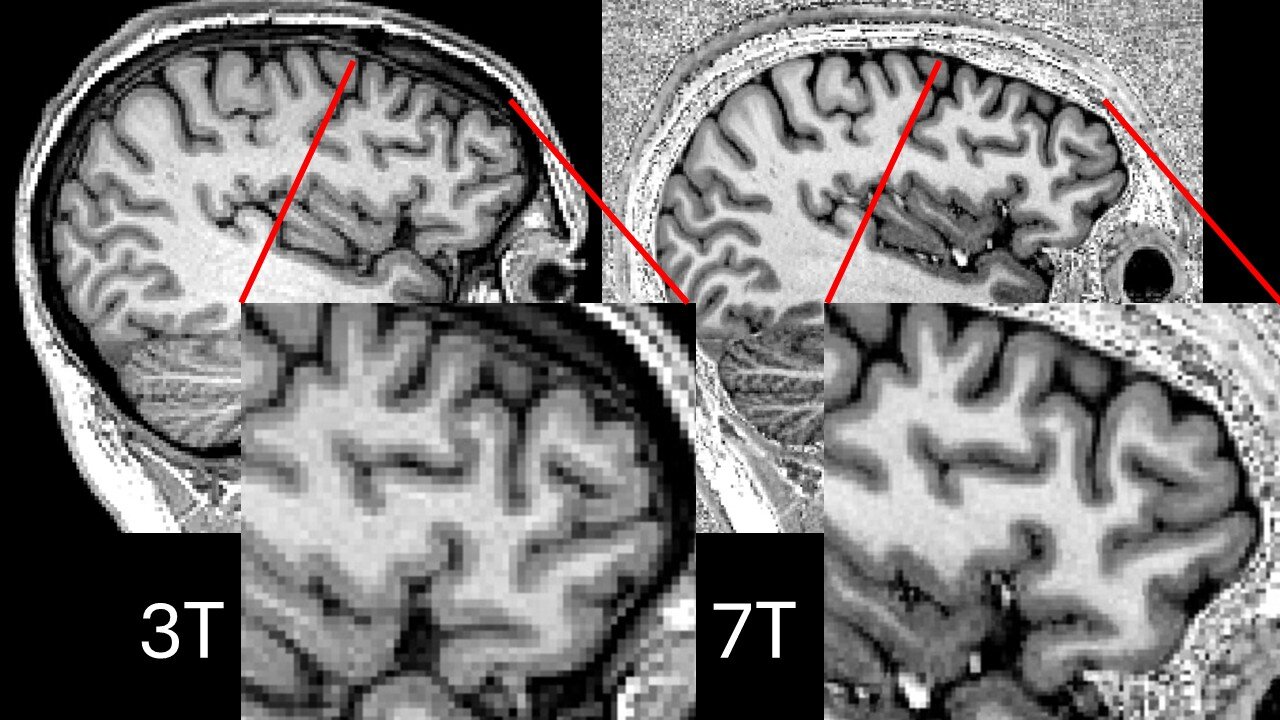

At the heart of this medical revolution is the ultra-powerful 7 Tesla (7T) MRI scanner. To put that in perspective, the standard MRI scanners found in most NHS hospitals operate at 1.5 Tesla. Some of the best machines, reserved for more complex cases, manage 3 Tesla. But the 7T scanner is more than twice as powerful—offering an unparalleled level of detail, akin to switching from an old tube TV to an ultra-high-definition display.

This technology allows neurologists to scrutinize the brain with microscopic precision, picking up subtle structural abnormalities—tiny lesions or areas of diseased tissue—that are the root cause of epilepsy in many patients. These lesions are often elusive on standard scans, hiding in plain sight, and their discovery can make the difference between an ongoing struggle with epilepsy and a life free from seizures.

Despite their promise, early 7T MRI scanners came with a frustrating flaw. The increased magnetic field strength, while offering superior detail, often produced signal dropouts—blackspots where the image would fade or disappear entirely. Tragically, these dropouts often occurred in the temporal lobes, which are precisely where most focal epilepsies originate.